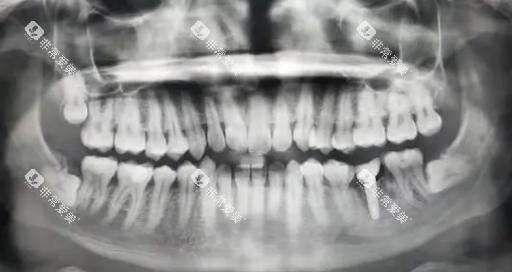

正常生长的智齿牙根与牙槽骨的关系相对简单,拔除时操作空间较为充足;而横着长的智齿,由于其生长方向与其他牙齿垂直,牙根往往会与邻牙牙根、下颌神经管等重要结构紧密相邻 。

拔除时,医生不光需要小心翼翼地避免损伤邻牙和周围组织,还可能要通过切开牙龈、去除部分牙槽骨等操作来获得足够的操作空间,才能顺利将智齿取出。